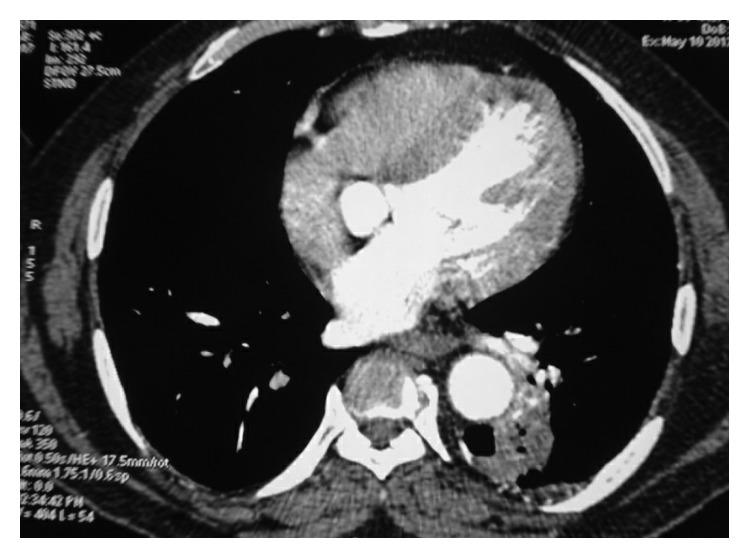

Pulmonary actinomycosis is an important differential diagnosis in patients with long-standing pulmonary infiltrates related to poor oral hygiene or compromised immune function. Up to a quarter of cases of thoracic actinomycosis are misdiagnosed as lung malignancy. Here, we report a 56-year-old man with a hypodense lesion in the left lower lobe presenting with recurrent massive haemoptysis for about one year. He underwent left lower lobe lobectomy due to intractable haemoptysis. Histopathological examination demonstrated actinomycosis infiltrating the left lower lobe. Rarity of the case was the presence of actinomycosis in an immunocompetent individual and without underlying preexisting lung disease. Also, intractable massive haemoptysis necessitating surgical excision which proved to be both diagnostic and curative due to actinomycosis is an unusual occurrence.